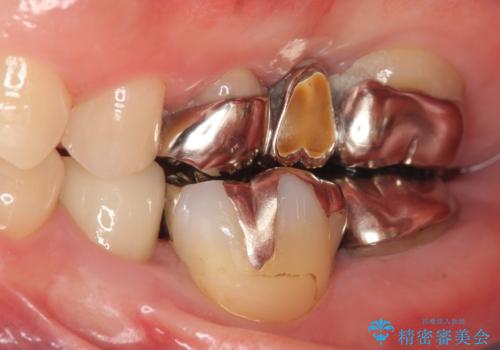

- 左下の奥歯がズキズキ痛むので診て欲しいといらっしゃった方の症例です。他院では5番目と7番目の歯を抜歯してインプラントと言われたが、出来れば歯を残したいとのことでした。

痛みの原因は6番目の虫歯であること、5番目、6番目の歯は歯茎より深い虫歯であり現状では保存が難しいことを説明した上で、歯を挺出させる部分矯正と歯茎を下げる歯周外科を行いました。

手術後歯茎の治癒を待ち、オールセラミッククラウンによる補綴を行いました。